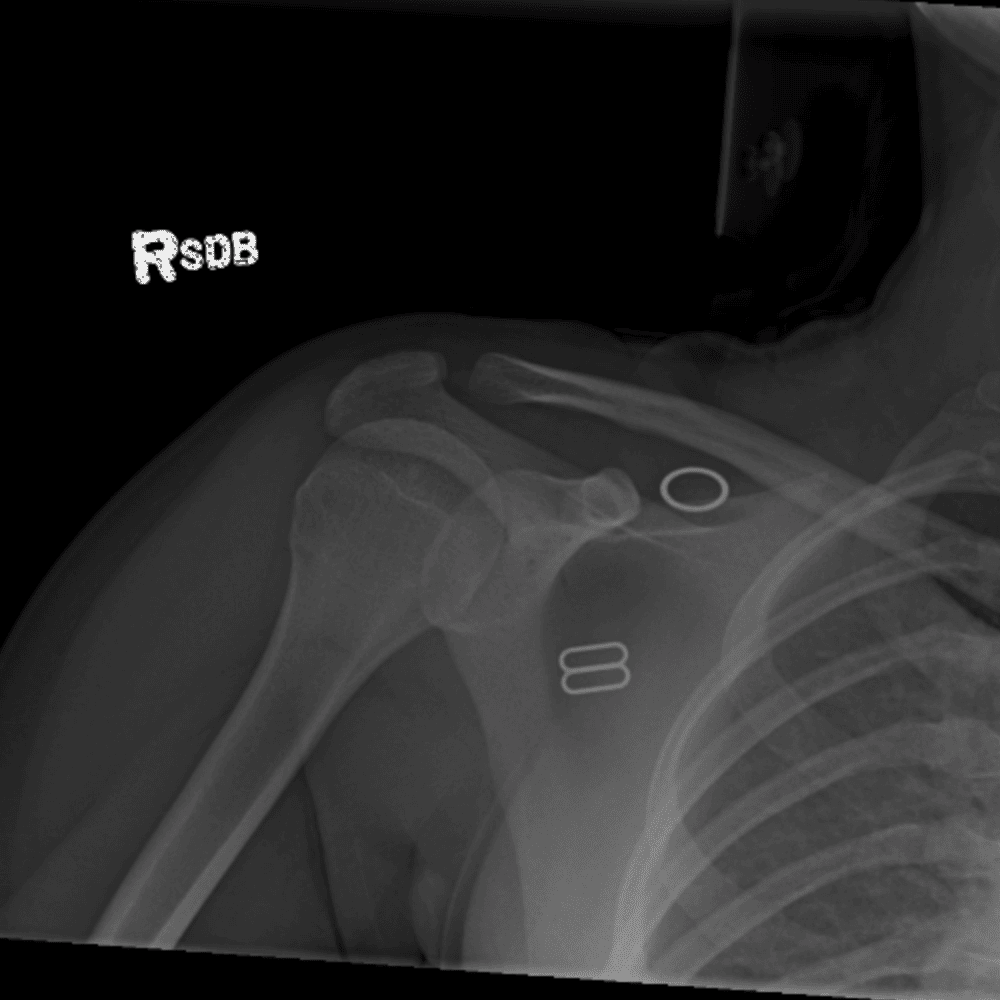

Simuliert den Dienst durch subtile oder schwierige Fälle und einige Normalbefunde.

30 Fälle